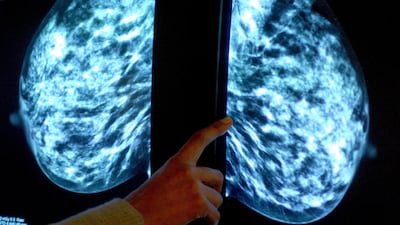

An artificial intelligence-based tool for estimating a newly diagnosed cancer patient’s chances for surviving long term has been developed by researchers.

The Cancer Survival Calculator uses machine learning to provide highly accurate, patient-specific survival estimates, refining prognosis evaluations to within nine to ten months of actual survival across various cancer types.

The calculator uses several factors to improve survival estimation, according to a study presented at the American College of Surgeons Clinical Congress 2023.

Unlike conventional methods that primarily depend on cancer staging, this tool incorporates a myriad influential factors ranging from patient age and tumour size to specific treatment variables, offering a more comprehensive and personalised survival prognosis.

The research primarily focused on patients diagnosed with breast, thyroid, and pancreatic cancers, because these cancers present diverse patient populations and survival rates.

Using an extensive data set from the National Cancer Database, the calculator was optimised using records of patients diagnosed in 2015 and 2017.

The data set encompassed 259,485 breast cancer patients, 76,624 thyroid cancer patients, and 84,514 pancreatic cancer patients, allowing the machine learning algorithms to identify and rank various factors influencing survival outcomes.

“There is a multitude of other factors that may influence a patient’s survival beyond just their staging criteria," said Dr Lauren Janczewski, lead study author and surgical resident at Northwestern University's McGaw Medical Centre in Chicago.

She further highlighted the tool’s ability to include specific tumour biomarkers and treatment variables, enhancing its accuracy and predictive capabilities compared with previous survival calculators.

The development process involved using three quarters of the collected data to train the machine-learning algorithms, with the remaining data used for validation, ensuring the prototype’s accuracy and reliability in survival estimation.

As the next step, the research team plans to enhance the user interface of the calculator, facilitate its implementation in clinical practice, and conduct pilot tests at selected cancer centres.

The ultimate goal is to expand the calculator's utility to include additional cancer types, helping healthcare practitioners improve cancer prognosis estimations and patient care.